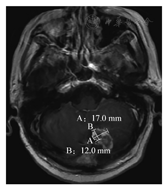

采用2015年发布的RANO-BM建议,依据2009年发布的RECIST1.1标准,评估中只测量脑实质内转移病灶,基线测量时靶病灶总数最多5个,可测量靶病灶需要实性强化最大单径≥10mm,不包括囊和腔[11],见图7。